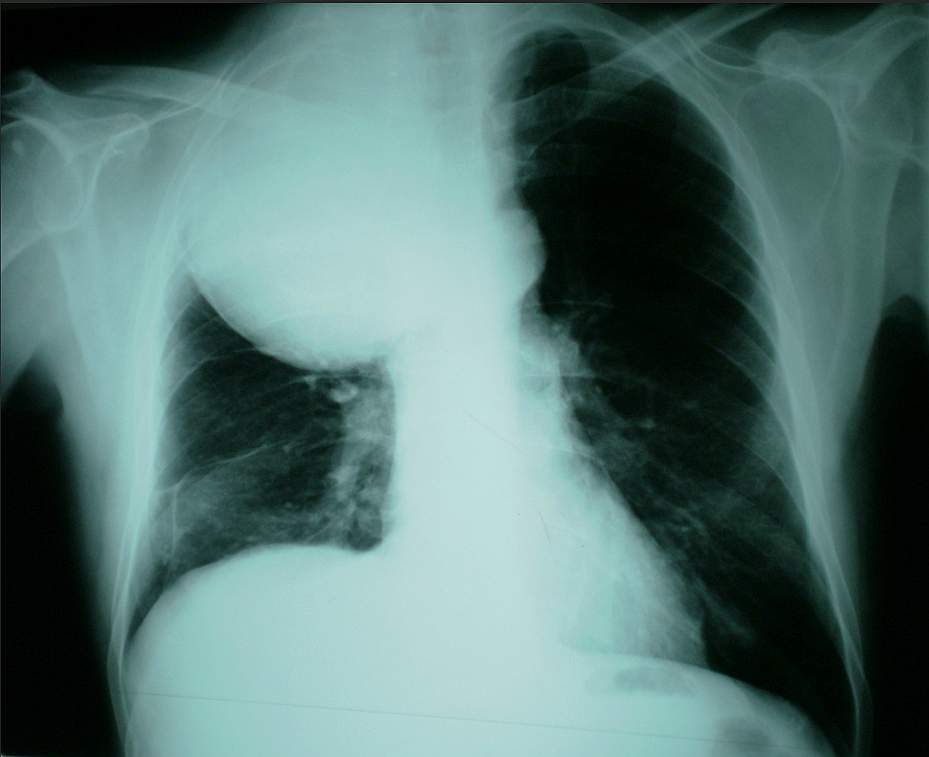

A 40-year-old Man with Cough and Dyspnoea Post category:Spot Diagnosis Post published:November 26, 2023 Share on Facebook Share on X (Twitter) Share on Pinterest Share on Email Share on Reddit Posteroanterior chest radiograph of a 40-year-old Man with Cough and Dyspnoea A 40-year-old man was referred to a pulmonary clinic with a history of cough and dyspnoea, at least for a month. What could be the diagnosis ? FULL CASE AND ANSWER Share on Facebook Share on X (Twitter) Share on Pinterest Share on Email Share on Reddit Read more articles Previous PostFacial Rash After Birth Next PostCrusted Erosions, Atrophic Scars and Fingernail Thickening You Might Also Like Patient with Diabetic Nephropathy and Secondary Hyperparathyroidism May 11, 2022 Patient with 3-month History of Coughing Reddish Sputum, Weight Loss, and Fever May 3, 2022 Dry, Scaly, Erythematous, and Annular Lesions on Face February 1, 2022